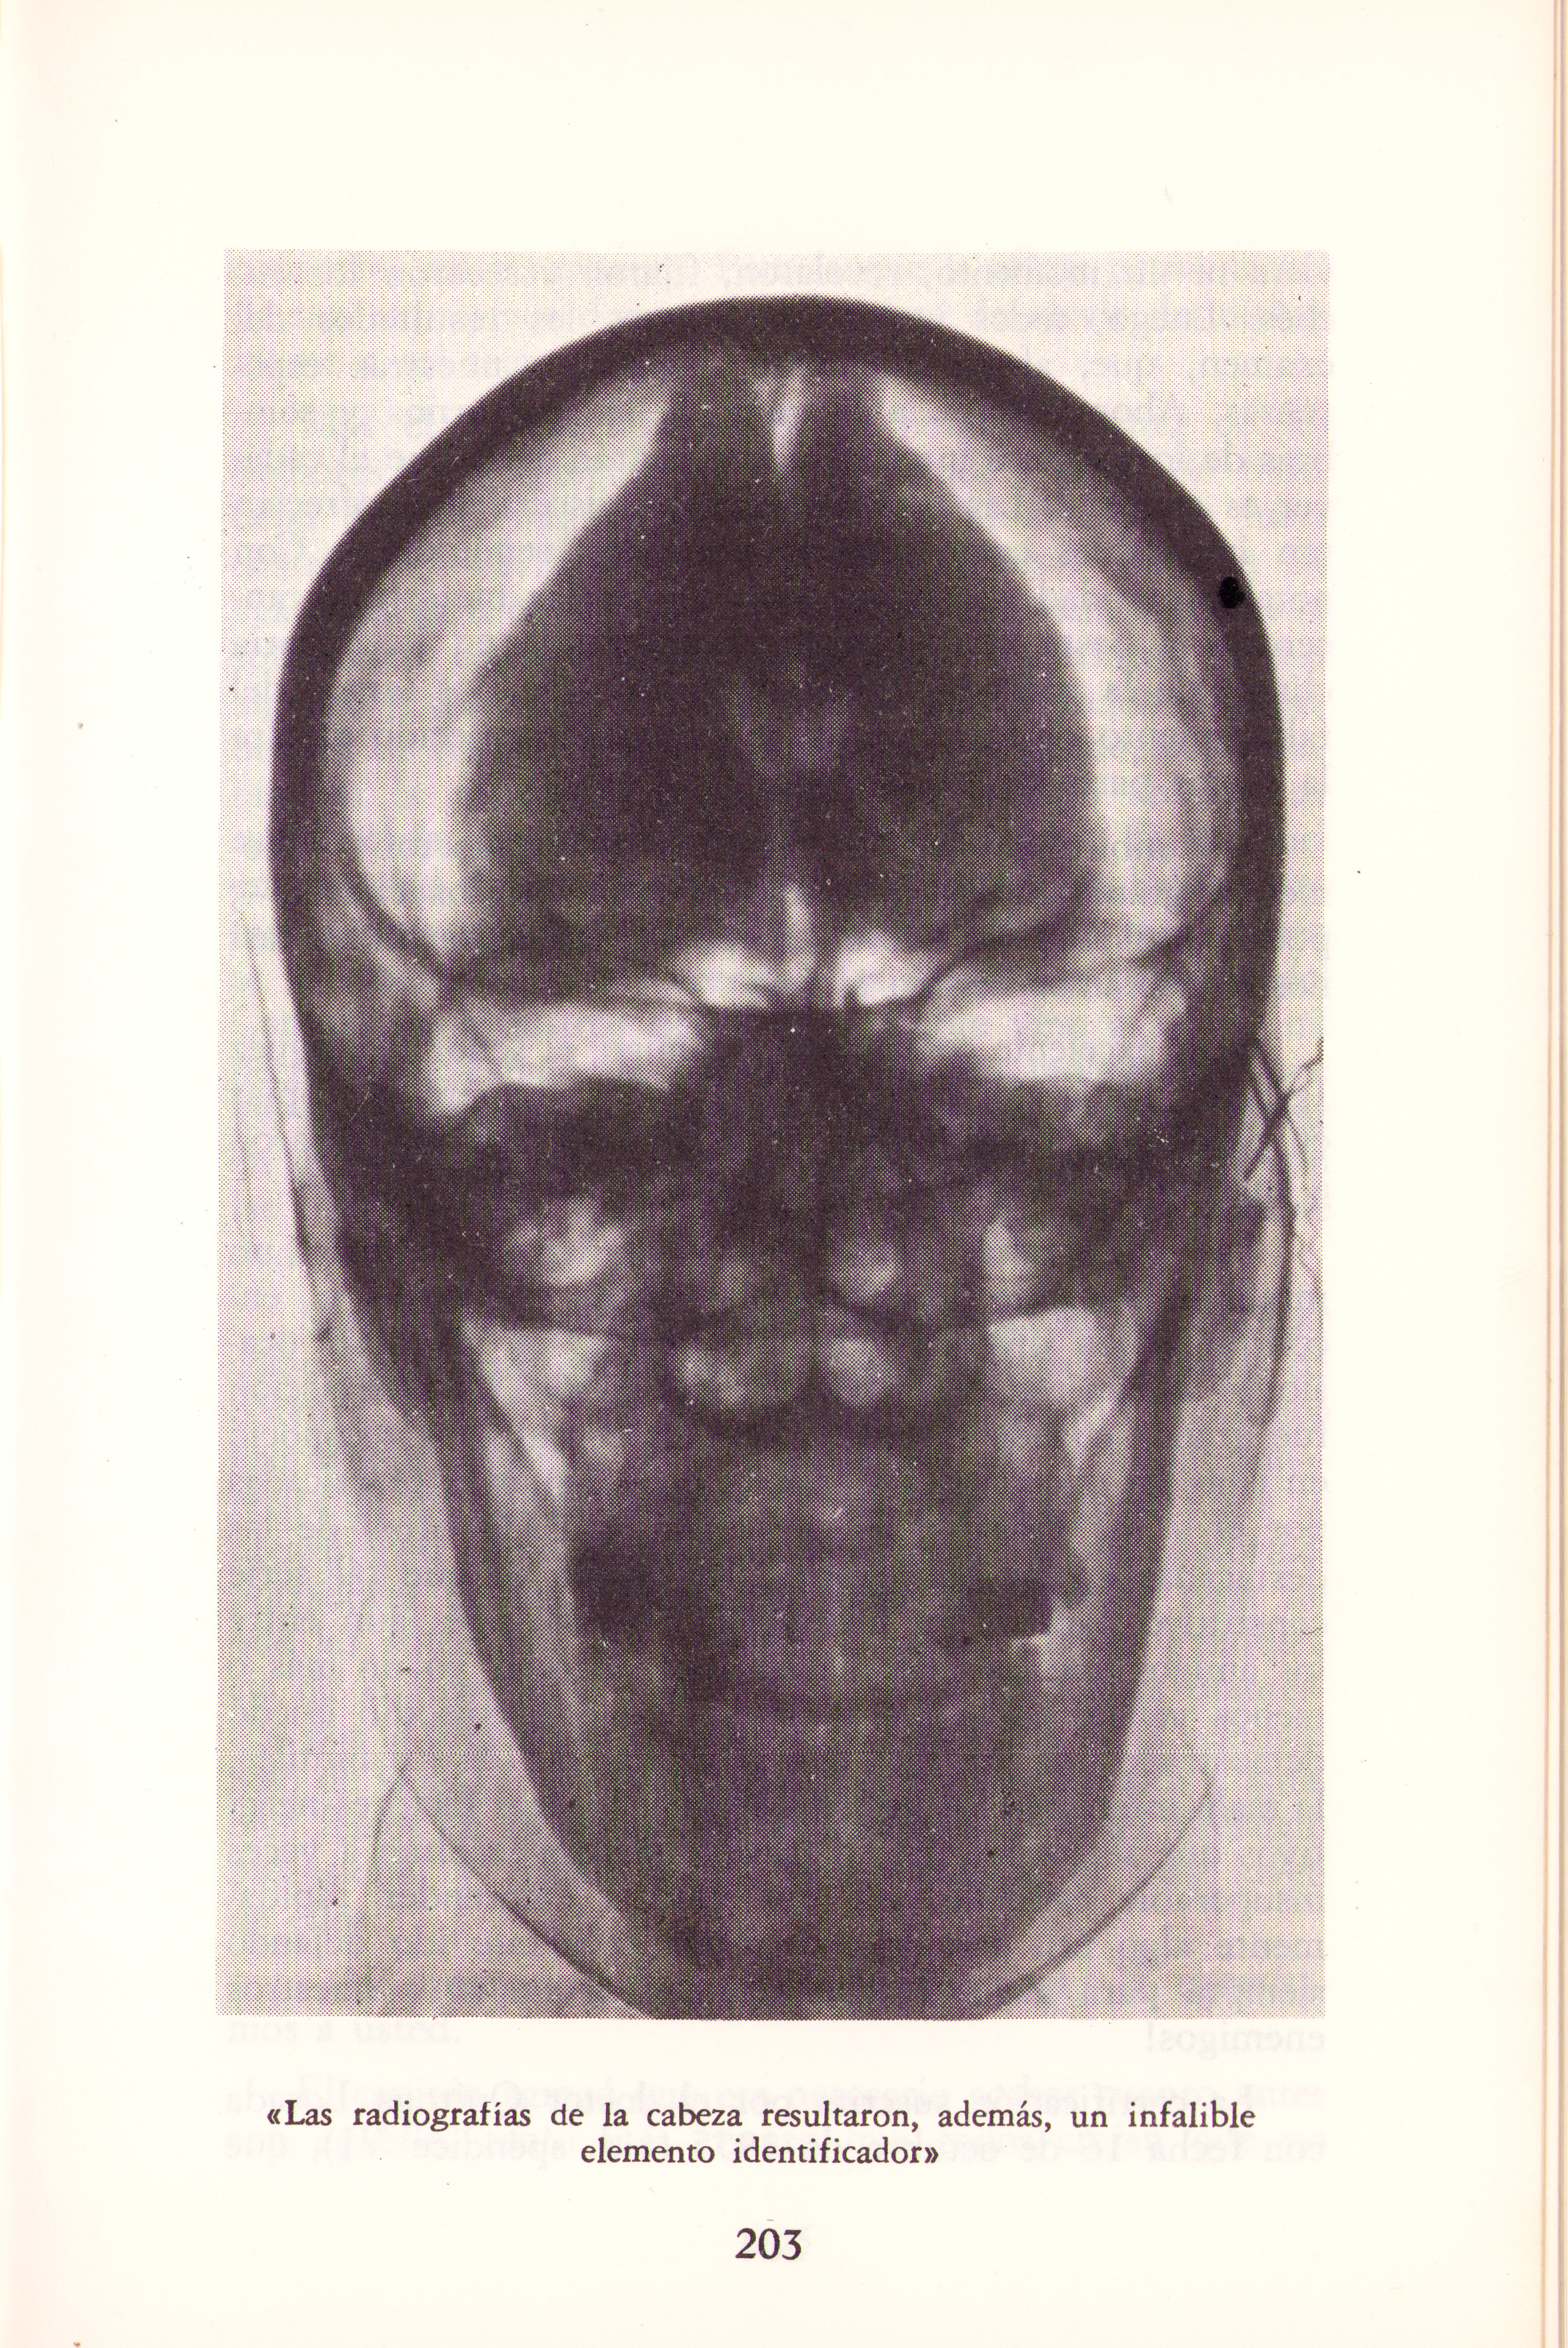

Radiografía Eva Peron

“…Las radiografías de la cabeza resultaron, además, un infalible elemento identificador”

Pertenece al libro “El caso Eva Peron”